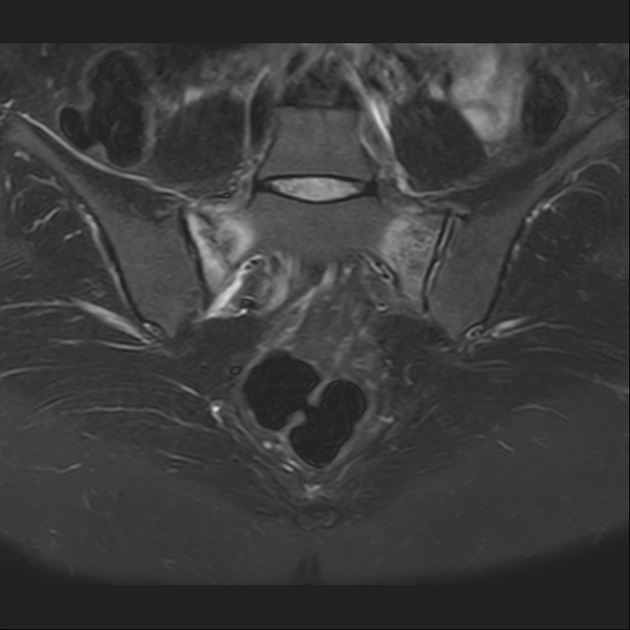

磁共振检查:

STIR

磁共振影像表现